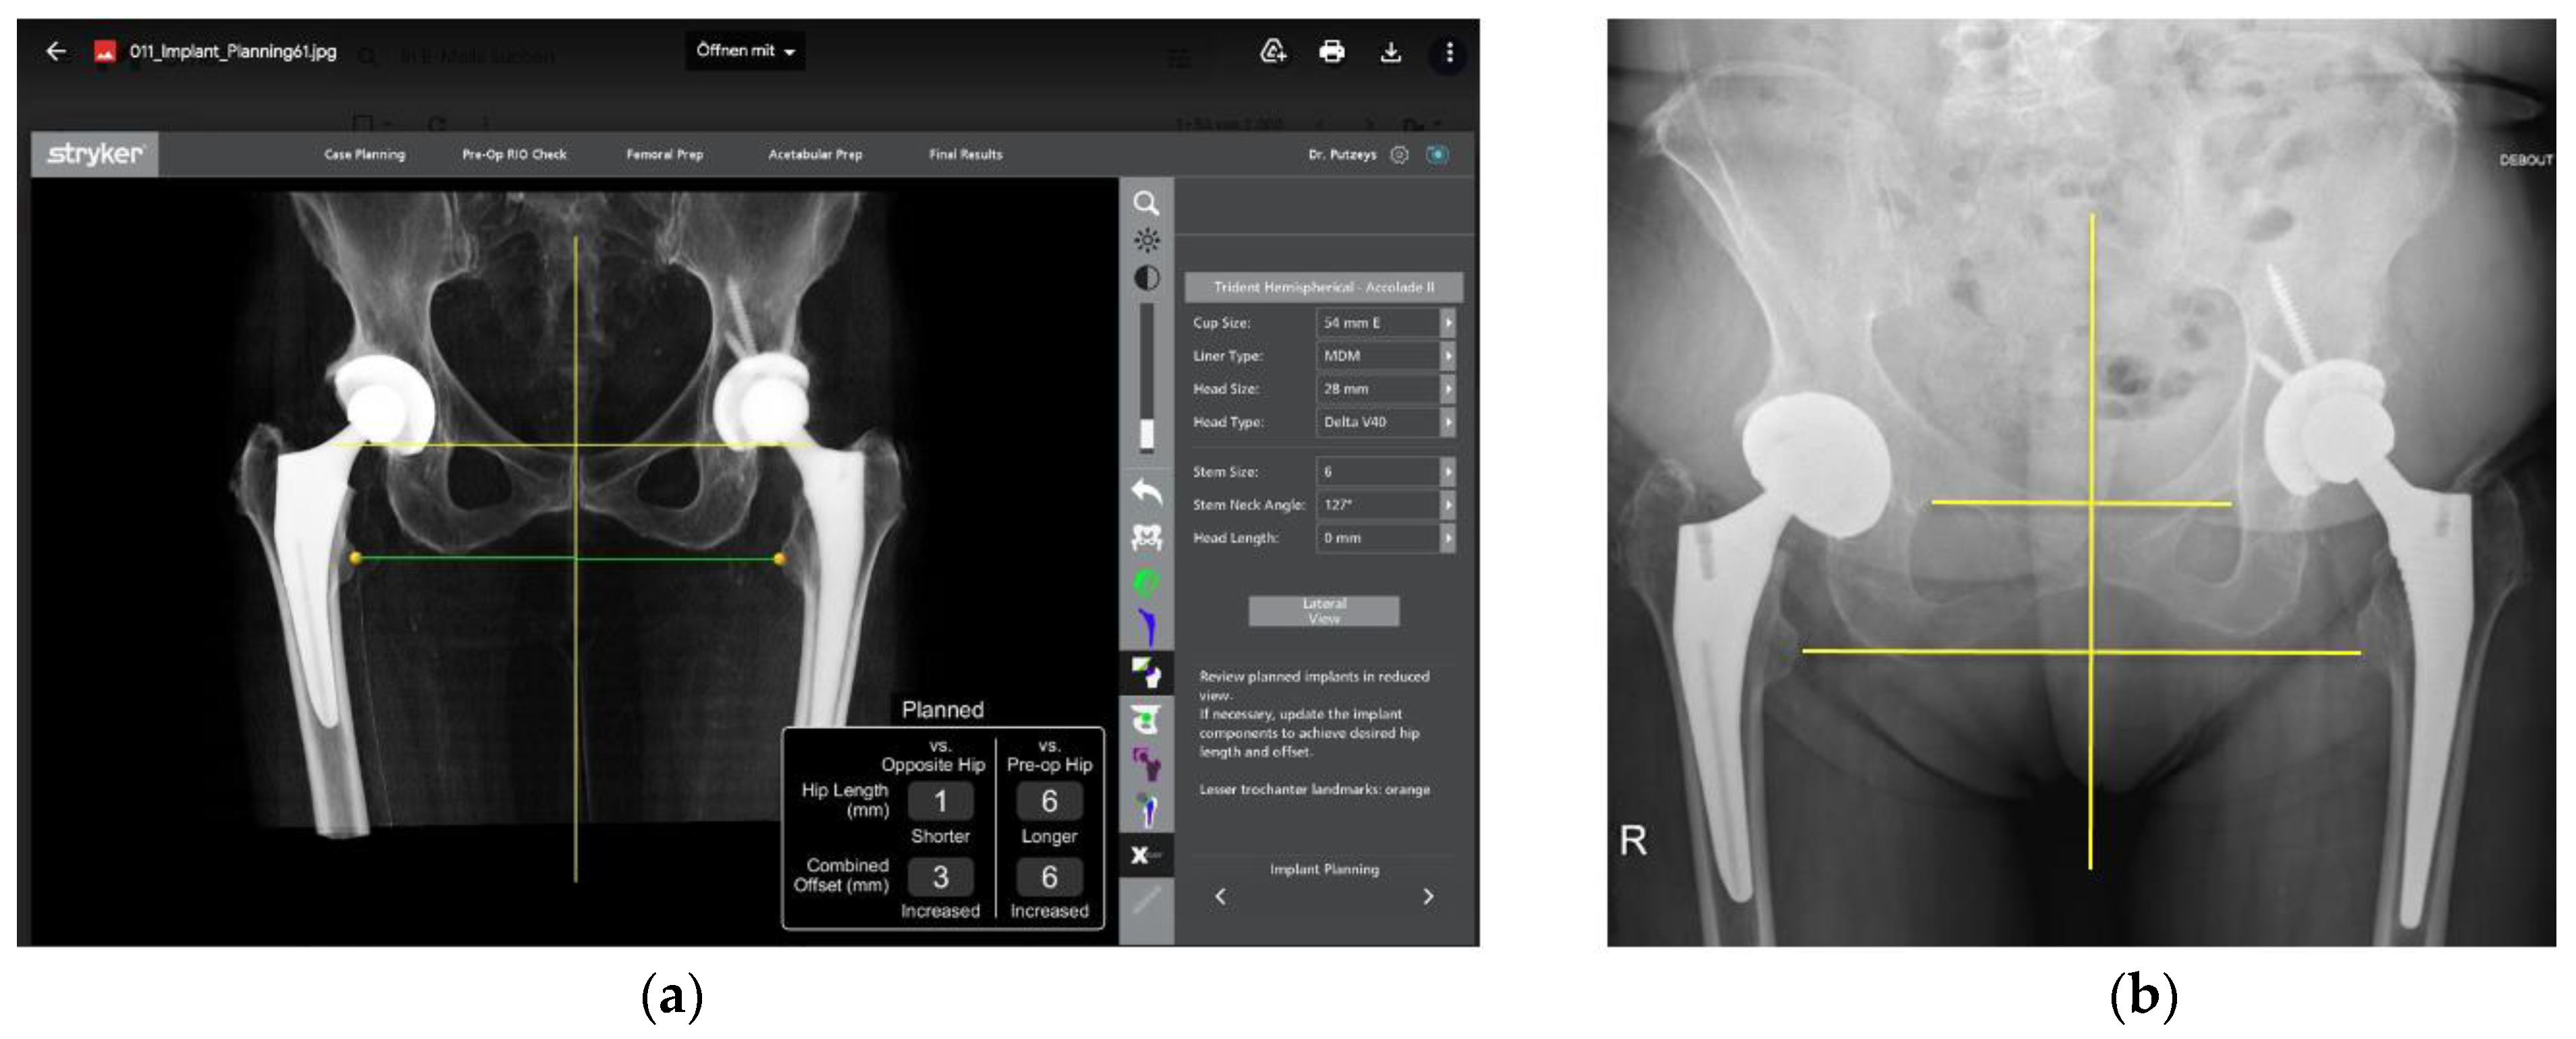

- The robotic software also enables preoperative and intraoperative visualisation of the anticipated postoperative X-rays accounting for any changes to the plan. In addition, the software allows for calculation of changes to the leg length offset compared to the preoperative and contralateral hips. In this case, the leg length was 1 mm longer compared to the opposite hip, and the combined offset was 6 mm increased compared to that preoperatively (Figure 12a,b).